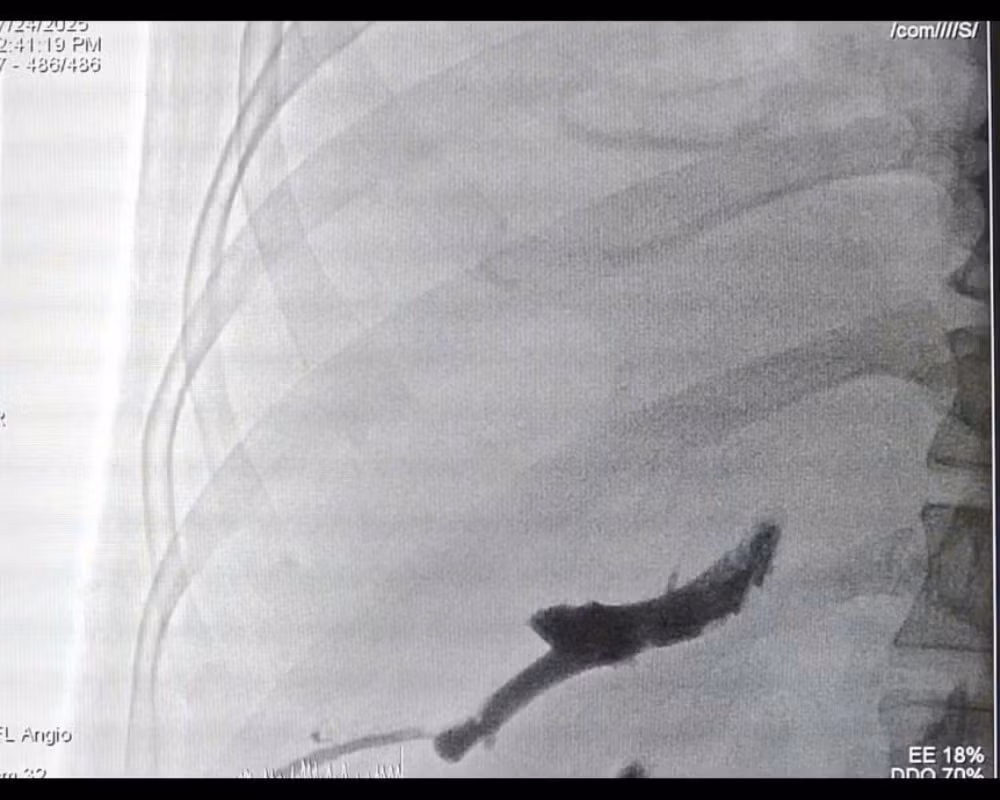

Gan phải và khối u giảm kích, phần gan trái lành phát triển phì đại - Ảnh BVCC

Ở giai đoạn hai, ê kíp phẫu thuật đã thực hiện cắt bỏ toàn bộ gan phải mang khối u, với khối lượng hơn 1,5 kg. Ca mổ thành công, bệnh nhân hồi phục tốt và không gặp biến chứng suy gan do thiếu hụt thể tích gan chức năng.